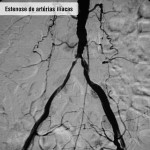

Tratamento endovascular

Pacientes com feridas necessitam de cirurgia na qual é feita punção na virilha, dilatação dos estreitamentos com balão e colocação de stent (molde metálico) para manter a artéria aberta. Com este procedimento, o paciente evita cortes, toma anestesia local e pode voltar para casa no mesmo dia (após seis horas de repouso) ou no dia seguinte. Para evitar novas lesões é imprescindível que a pessoa mude seus hábitos de vida, optando por um estilo mais saudável – inclui-se aí a prática regular de exercícios, a suspensão do fumo e o controle do colesterol e do diabetes.

Doença obstrutiva segmento aorto ilíaco – Caso 02